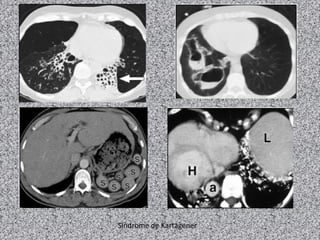

Metade dos casos é associdas a situs inversus

(síndrome de Kartagener):

Combinação de situs inversus, sinusite crônica e

bronquiectasias.

Radiografia de tórax:

Normal ou achados não específicos como

espessamento brônquico e aumento da trama

broncovascular;

Dextrocardia e situs inversus em 50% dos casos;

Sinais de bronquiectasias.

TCAR de tórax:

Bronquiectasias (achado principal) geralmente do

tipo cilíndrico;

Nódulos centrolobulares e opacidades lineares ou

ramificadas;

Áreas de diminuição da atenuação e perfusão e

aprisionamento aéreo à expiração.

Síndrome de Kartagener